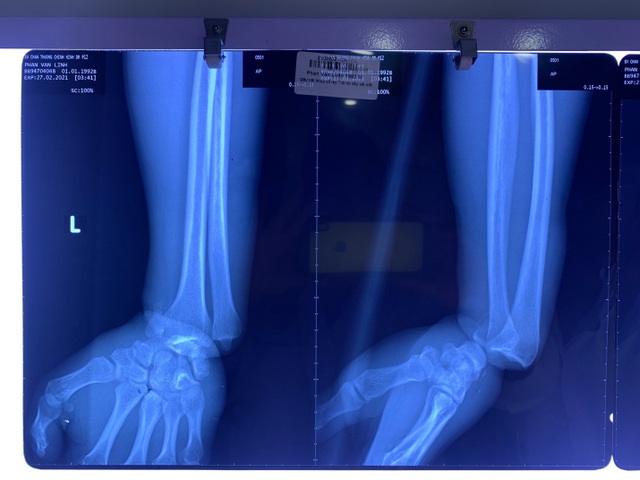

Tai nạn xảy ra khiến nam công nhân đau đớn kêu cứu và được đồng nghiệp đưa đến bệnh viện cấp cứu trong tình trạng bàn tay đã tím tái mất cảm giác. Kết quả chụp X-quang trước mổ ghi nhận, bệnh nhân bị gãy, trật khớp cổ tay trái. Ngay lập tức các bác sĩ chỉ định thực hiện cuộc phẫu thuật ở giờ thứ 8 sau tai nạn.

Trong quá trình mổ, bác sĩ ghi nhận ngoài trình trạng gãy, trật khớp, vị trí cổ tay của bệnh nhân còn bị dập tắc bó mạch thần kinh trụ, dập động mạch quay, dập thần kinh giữa, nhổ dập nát các gân cơ, gân duỗi các ngón, dập siết cổ tay, bàn tay tím.